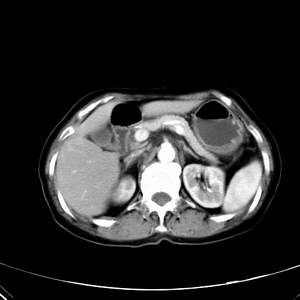

患者,女性,77岁,右上腹胀痛月余。afp正常。ca125升高。即往无肝炎病史。

肝右叶病灶是胆管细胞癌吗?门静脉右支癌栓形成?右侧肾上腺有问题吗?

最后5幅图片是延时7分钟的。门静脉右前支内有充缺吗?如有,肝血管瘤不好解释。

支持考虑胆管细胞癌;但门脉右支癌栓不明显.

病灶渐进性向心性强化,延时病灶中心见条片状高密度影,局部见肝包膜回缩征,结合病人无肝炎病史,考虑肝右叶胆管细胞癌,门脉右支癌栓形成。